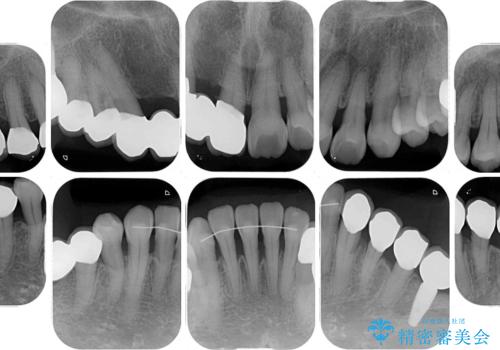

数多くの外科処置を行ったため、治療期間は長期間となりました。

一方、外科処置をしっかりと行ったことで、歯周病の状態は改善され、安定した状態にしあげることができました。